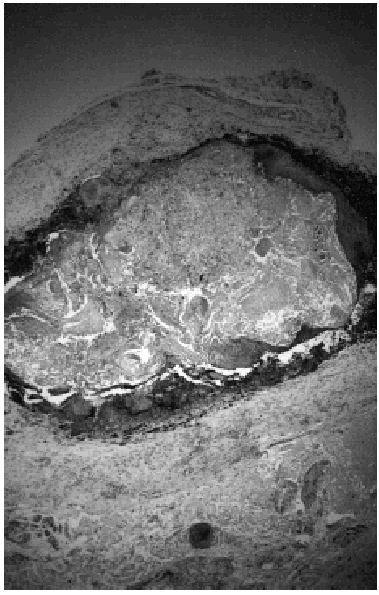

Bajo la sospecha de quiste epidermoide se procedió a la extirpación completa de la lesión bajo anestesia local. El examen macroscópico de la pieza evidenciaba que se trataba de una neoformación encapsulada de 1,8 x 1,6 x 1,5 cm, con tonalidades negruzcas en alguna zona. El estudio histopatológico mostró un pilomatricoma en el que se apreciaba gran cantidad de pigmento melánico en el interior, tanto de las células basófilas como de las fantasmas, así como en macrófagos del parénquima (fig. 1). Además se podía apreciar la presencia de algunos melanocitos dendríticos intercalados entre las células del tumor (fig. 2).

Fig. 1.--Células epiteliales basófilas en la periferia, en transición hacia células fantasma en el interior. Pigmentación periférica (HE x 200).